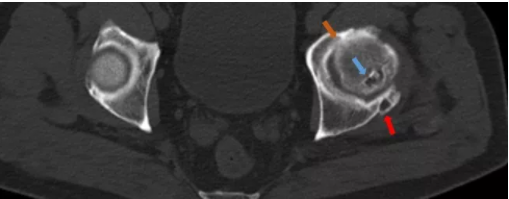

病例2-1 示左侧股骨头后缘密度不均,可见囊状透亮区(蓝色箭头),髋臼关节面下亦可见囊状透亮区(红色箭头),髋关节面变窄(橙色箭头)。

病例2-2 示右侧股骨头内见星芒状的线形高密度硬化影;右侧髋关节边缘股骨头及股骨颈明显骨质增生。